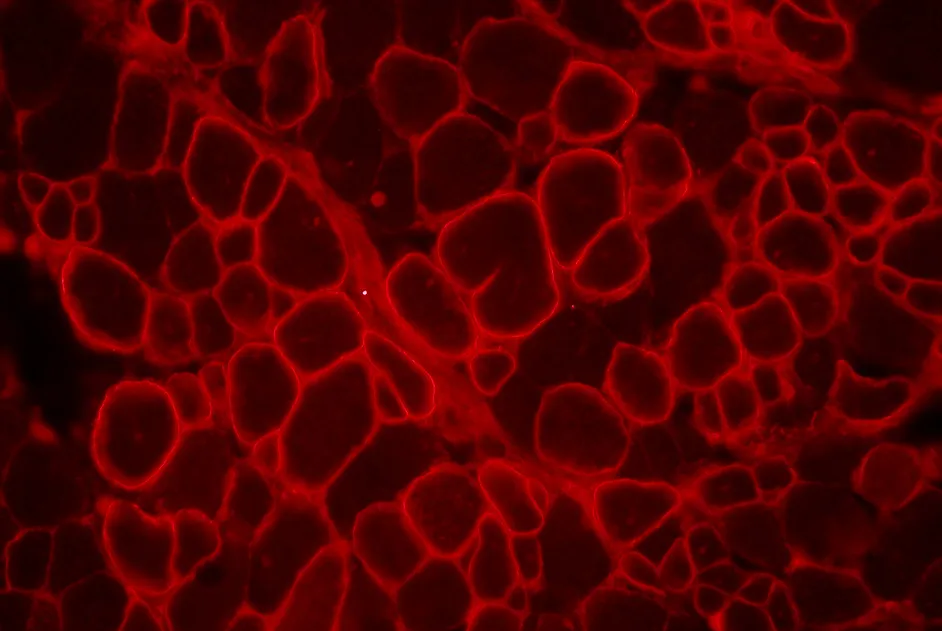

Pour contourner cet inconvénient, une équipe hollandaise a associé un peptide candidat aux oligonucléotides antisens qu’elle a injectés à des souris modèles de DMD. Ses résultats publiés dans un article en décembre 2013 montrent que l’association de ces 2 produits s’est efficace puisqu’elle a amélioré le ciblage des oligonucléotides dans les muscles et le cœur ainsi que l’efficacité du saut d’exon de la dystrophine au niveau du cœur et du diaphragme.